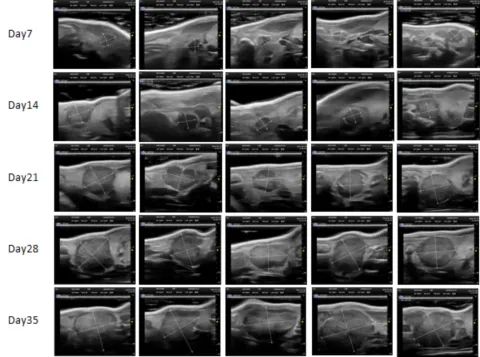

PDX Model (Growth Curve)

部分不朽情缘mg官网PDX原位模型展示